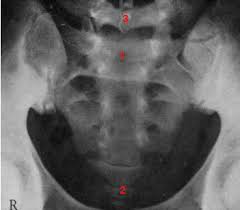

Radiopelvimetría

Se trata de radiografías practicadas en la mujer embarazada al final del embarazo (finales del octavo mes e inicio del noveno). Si se sospecha que tiene la pelvis demasiado estrecha o con alguna anomalía, que impedirían que el bebe baje de forma adecuada y sin problemas por el canal de parto, permite medir las dimensiones de su pelvis ósea y comprobar si el parto se puede efectuar por vía normal o se requiere una cesaría.

La radiopelimetria determina de forma exacta la relación entre la pelis y la cabeza del bebe atreves de una radiografía que mide los espacios óseos, durante la radiopelvimetría, los diferentes diámetros por los que el niño debe pasar se miden mediante varios clichés; los resultados se comparan con normas y dimensiones del feto, que se han calculado a partir de la ecografía. Este examen puede ser practicado por radiología convencional (rayos X) o por escáner y es totalmente indoloro. Se prescribe en caso de duda sobre las dimensiones y la forma de la pelvis, cuando hay antecedentes de cesárea, si el feto se presenta de nalgas y en ciertos casos de embarazo de gemelos.

Proyecciones

AP: acostado en la camilla permitirá ver crestas iliacas, y la posición de el bebe, principalmente si cabeza.

Lateral: estar permite ver las primeras vertebras lumbares y el sacro, detectando el grado de sacralización de la quinta lumbar lo cual tiene consecuencias segundarias